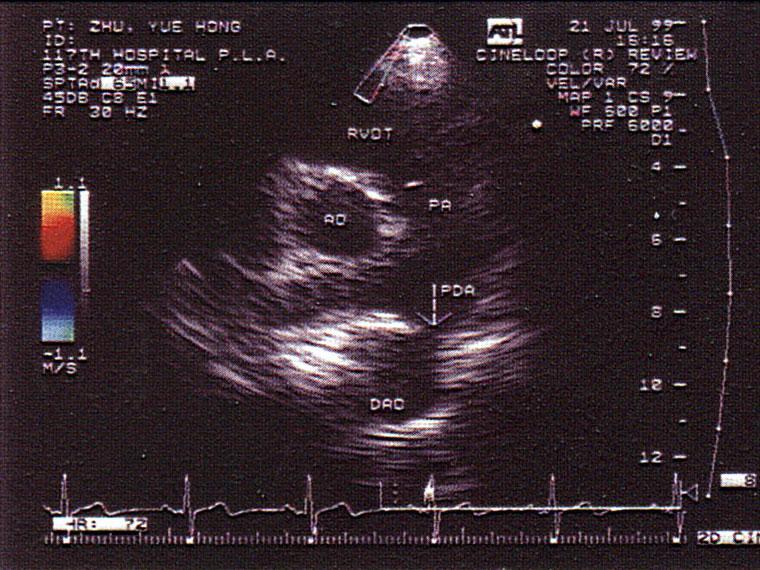

问题 该病例最可能的诊断?(?)

选项 A.主肺动脉间隔缺损 B.动脉导管未闭 C.冠状动脉—肺动脉瘘 D.主动脉窦瘤破裂 E.房间膈缺损

答案 B